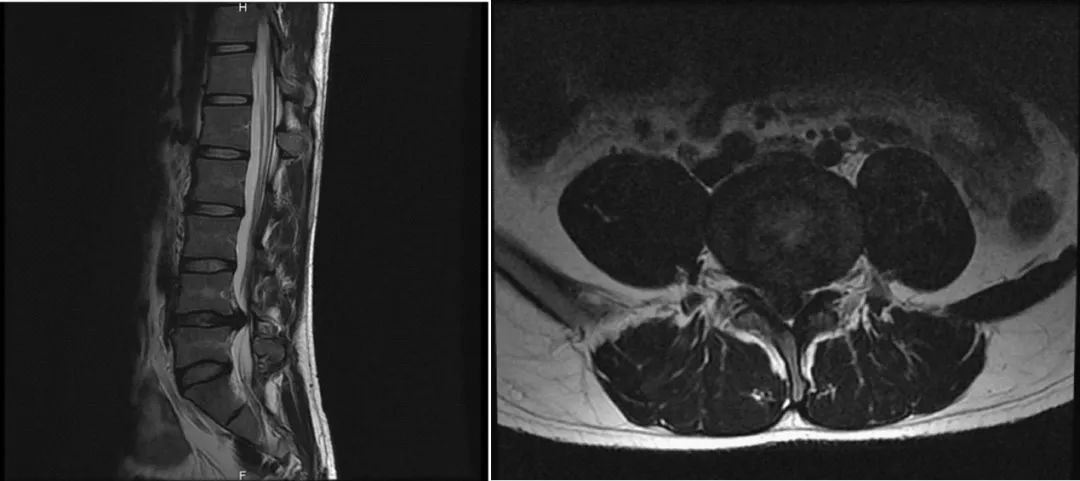

舒同学术前腰椎MRI:腰4/5巨大椎间盘髓核突出,压迫神经根

舒同学(化名)是在海外求学的中山大学研究生,美国洛杉矶大学戴维斯分校统计学专业在读博士生。24岁的他,风华正茂,朝气蓬勃。然而从去年10月份起,他经常感腰部疼痛,间歇性发作,久坐、久站、弯腰负重后腰痛加重,严重影响学习与生活。美国是世界上医疗体系最发达的国家之一,他满怀希望的去当地医院求医,美国医生告诉他是“腰肌劳损”,建议他做理疗、牵引,辅以口服消炎镇痛、肌松药物等保守治疗。然而坚持治疗了2个月,收效甚微,病情反而进一步恶化。2019年12月底起出现了右下肢麻痛症状,呈放射性,由右侧臀部经大腿后外侧至小腿前外侧、足背,腰腿痛严重时甚至让他凌晨睡不着觉,睡到自然醒对他来说变成了一件奢侈的事。通过MRI检查发现,舒同学腰4/5巨大椎间盘突出,向后侧压迫神经根。“腰椎间盘突出症”这个病让在异国他乡艰难求学的舒同学十分困扰。